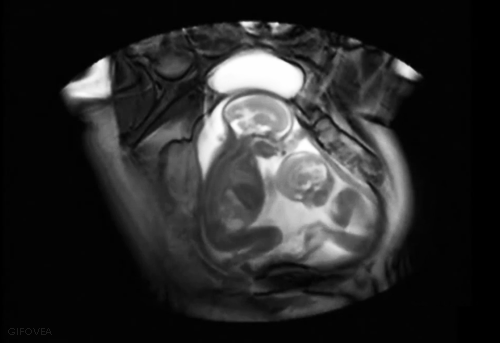

Gemelos en útero

![]() |

| Gemelos en útero |